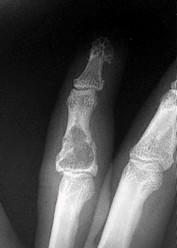

- الأشعة السينية (X-rays): هي الخطوة الأولى في تقييم الكسور، الخلوع، وتغيرات التهاب المفاصل. تساعد في تحديد مدى تدهور العظام والمسافات المفصلية. على سبيل المثال، تُظهر صور الأشعة السينية كسور السلاميات

أو كسور قاعدة العظم المشطي الخامس

، بالإضافة إلى علامات مثل "الدمعة الشعاعية" (Radiographic Teardrop) في الرسغ التي تمثل الزاوية الزندية الراحية الحرجة للكعبرة البعيدة

. - الأشعة المقطعية (CT Scan): توفر صوراً تفصيلية ثلاثية الأبعاد للعظام، وهي مفيدة جداً لتقييم الكسور المعقدة، مثل كسور العظم الخطافي (Hamate Hook Fracture) التي قد لا تظهر في الأشعة السينية العادية